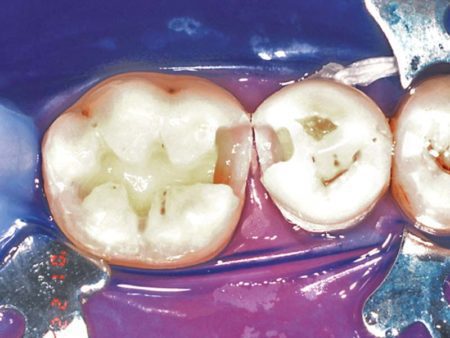

Fig. 1: Apply Etch-Rite™ to the cavity prep for 15 seconds

Fig. 2: Rinse and leave dentin moist for wet bonding technique

Photos courtesy of Dr. C. H. Pameijer